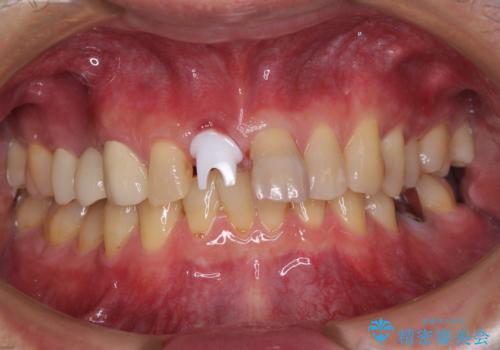

補綴治療としては、インプラントあるいはブリッジの2つがありますが、患者様と相談した結果、インプラントによる補綴治療を選択することとなりました。

咬合力が非常に強いため、インプラントにも過度な力の負担が発生する恐れがあります。

長期間安定して使用いただくために、睡眠時のマウスピースの装着による咬合力の分散が必要となります。